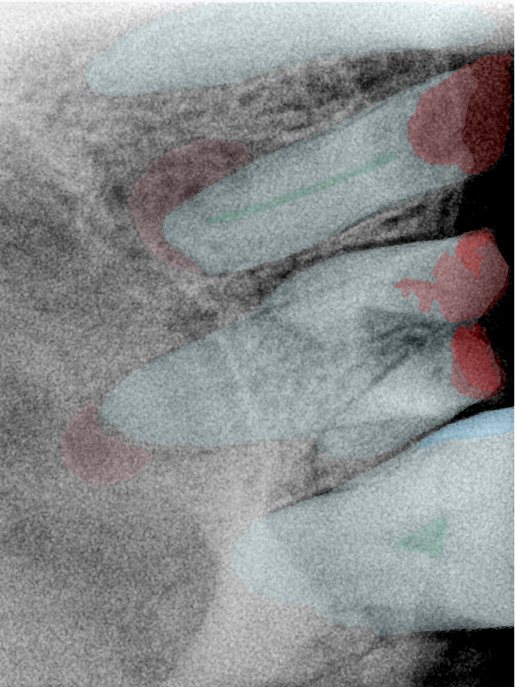

CR/DR 牙齿分割阶段记录

当前进展

- 完成了 CR/DR 牙齿相关分割训练

- 当前结果已经达到阶段预期,但仍有细节问题需要继续处理

相关测试

遇到的问题

- 训练过程中出现过 mask 下移问题

- 部分结果会出现 box 填充异常

- mask 边缘仍然有比较明显的锯齿感

第三版算法分辨率效果比较

| 编号 | 原图 | 第一版 | 第二版 | 第三版 1216x1600 | 第三版 768x1024 | 第三版 1120x1120 |